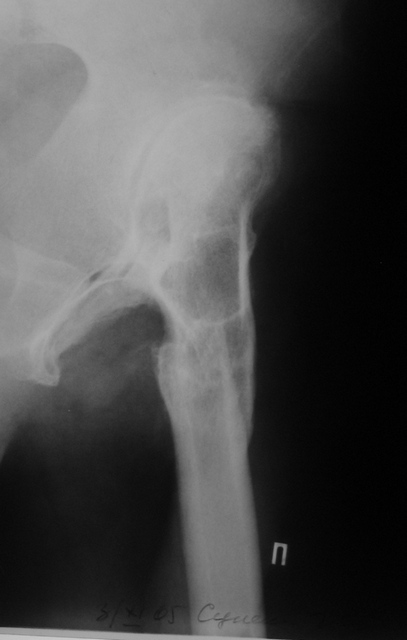

Выполнена одномоментная коррекция деформации, эндопротезирование DePyu Pinnacle-AML.Пластинка с деротационной целью. При использовании ножки с прямоугольным сечением, думаю можно и без нее